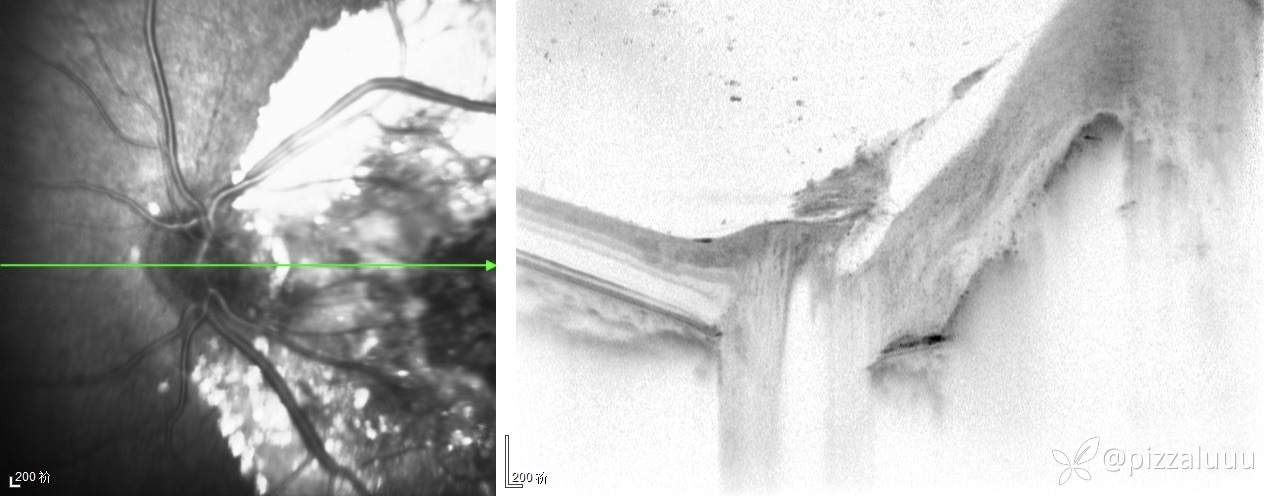

今天补充了FFA、AF和眼底照相。很典型的coats,后极部视网膜可见块状不规则而隆起的黄色渗出。AF可见病灶处低自发荧光。FFA所见:视网膜毛细血管扩张迂曲及异常血管形态,以小动脉明显,管壁呈囊样扩张,有梭形、串珠样动脉瘤。大片无灌注区。异常血管早期渗漏明显,形成强荧光斑,晚期荧光融合。由于大片黄白色渗出位于外丛状层,对视网膜血管荧光影响不大。可看到脉络膜背景荧光遮蔽。